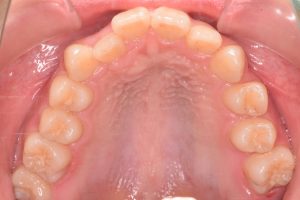

上あご

0000000006

0000000026

0000000077